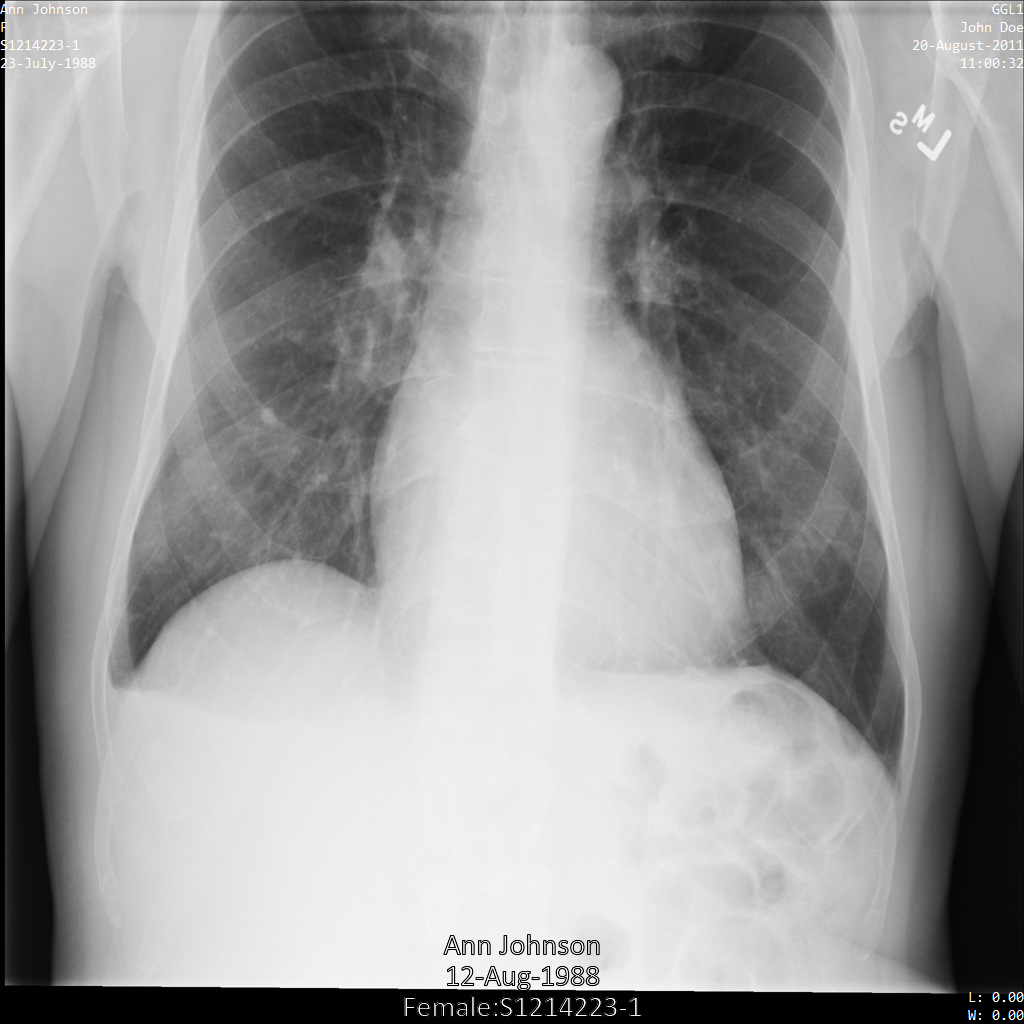

Cada uma das secções seguintes fornece exemplos de como remover a identificação dos dados DICOM usando vários métodos. É fornecida uma saída da imagem desidentificada com cada amostra. Cada exemplo usa a seguinte imagem original como entrada:

Pode comparar a imagem de saída de cada operação de desidentificação com esta imagem original para ver os efeitos da operação.